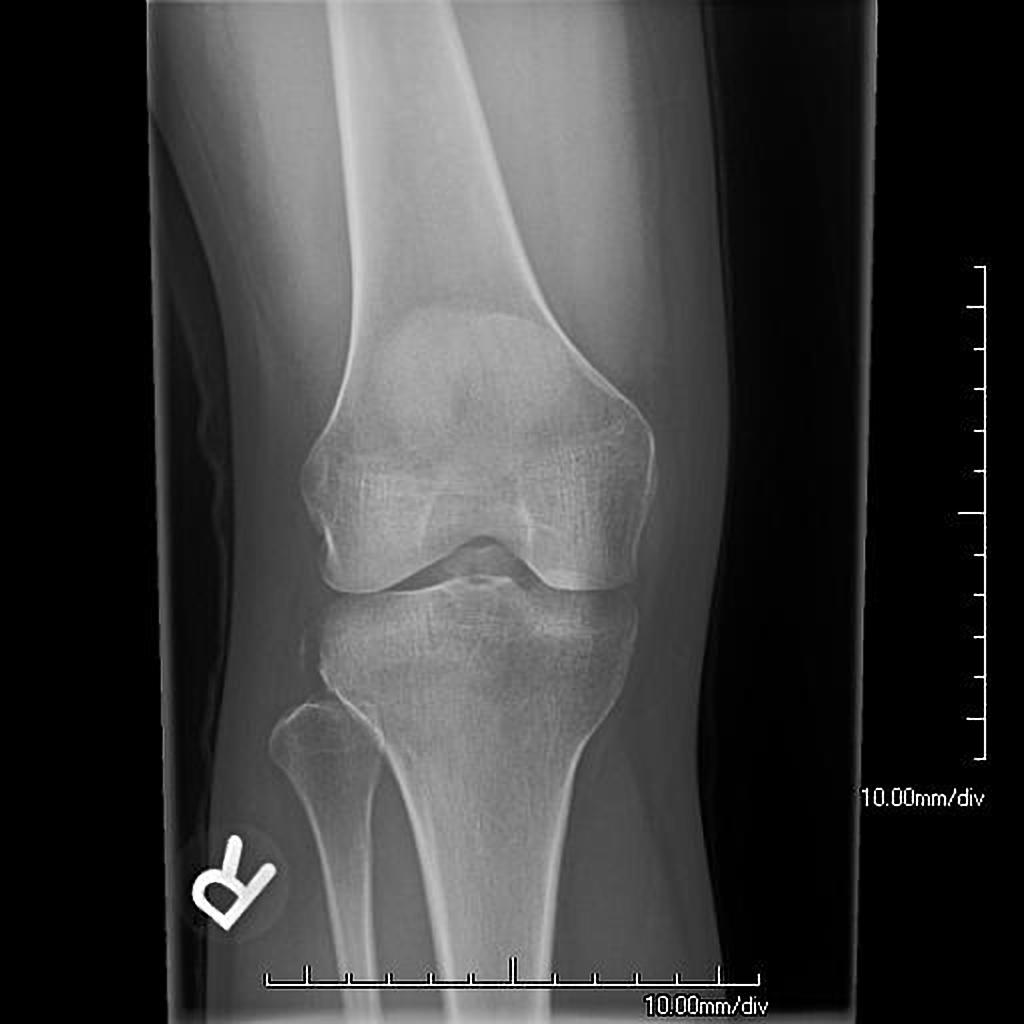

Tibial spine fracture with anterior cruciate ligament avulsion type 4 Cpt Code For Tibial Avulsion Fracture A probe is used to assess the lateral meniscus and cartilage. The current procedural terminology (cpt ®) code 27792 as maintained by american medical association, is a medical procedural code under. Arthroscopy procedures are the gold standard for the management of tibial spine avulsion. But i'm not sure if 27428 for acl repair of the avulsion is coded in. Using. Cpt Code For Tibial Avulsion Fracture.